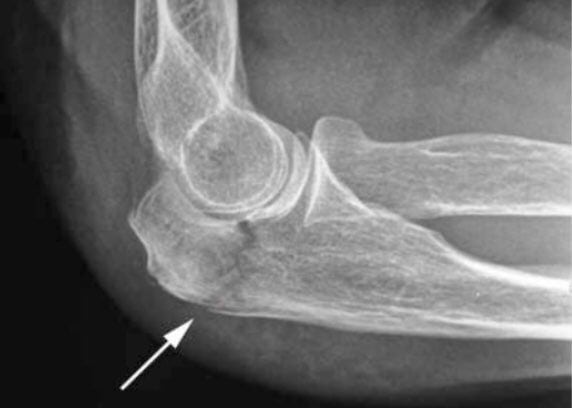

Чтобы выявить причину болей в локте, человеку требуется пройти обследование. В первую очередь, всем больным врачи делают рентгенографию локтевого сустава в 2-х проекциях. Она позволяет выявить грубые изменения в костях, которые появляются при артрозе и тяжелых хронических артритах.

На рентгенограммах нередко можно обнаружить и признаки эпикондилита: локтевые шпоры, участки эностоза, снижение плотности костной ткани и периостальные разрастания в области надмыщелков.